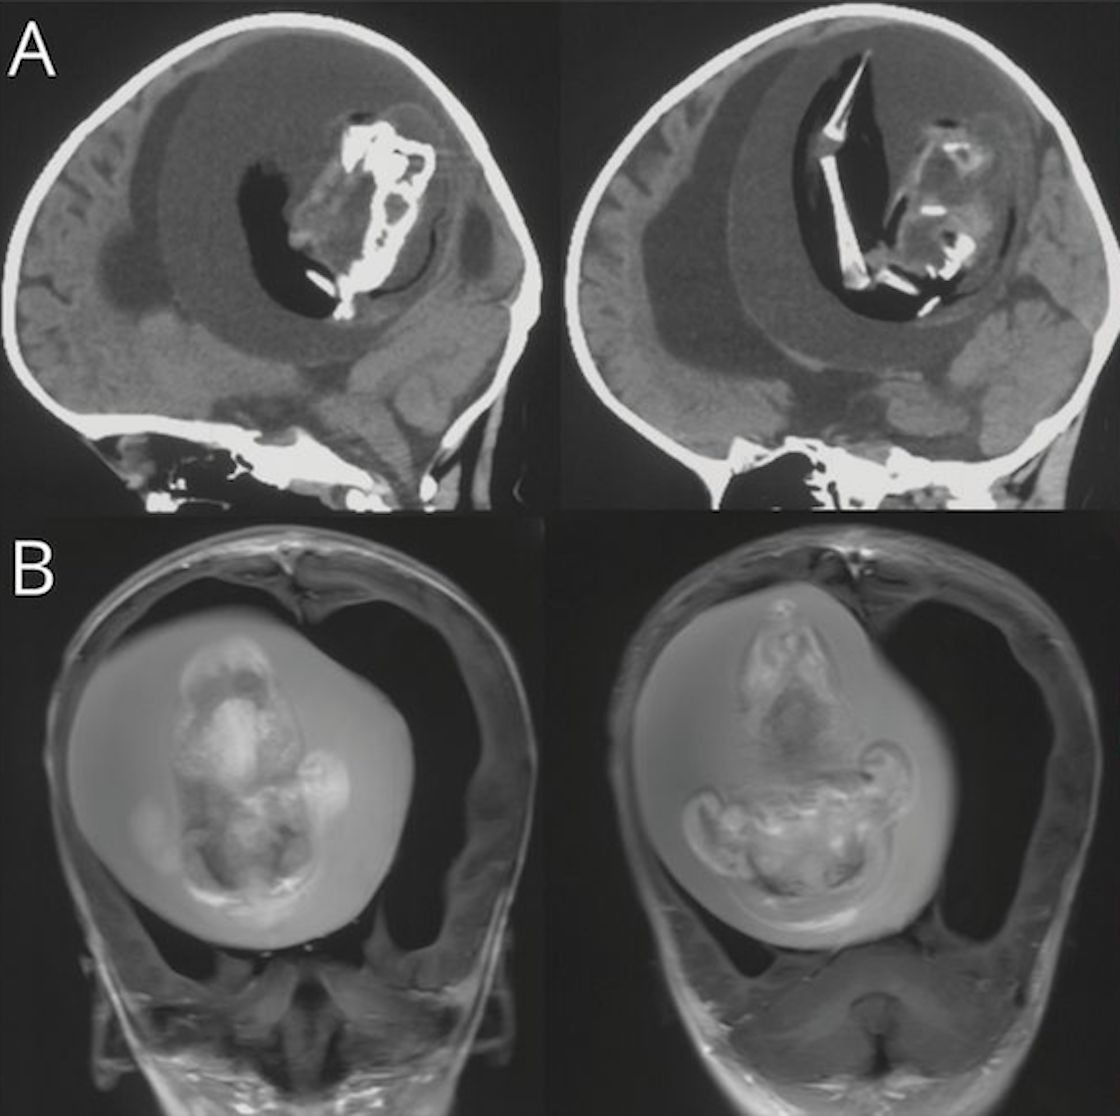

Sí, en la investigación que presentaron, explicaron que tras el sorprendente descubrimiento, se le practicó una intervención quirúrgica a la niña para extraerle el feto de su hermano gemelo.

En el estudio de los científicos chinos se explica que la masa que se extirpó de la cabeza de la bebé, un “gemelo diagnóstico monocriónico malformado”, ocurrió porque en el útero de la madre ambos fetos compartieron la misma placenta; sin embargo, tenían sacos amnióticos separados, que son los encargados de protegerlos mientras están en desarrollo.

Con esto, los expertos suponen que el feto se alojó en el cerebro de la niña durante un proceso de desarrollo llamado “plegamiento de la placa negral”, el cual es muy importante para la formación de la estructura del cerebro y la médula espinal.

Al darse cuenta del “feto en feto”, y practicar la cirugía, se dieron cuenta que el gemelo ya mostraba señales de desarrollo, como una columna vertebral, dos huesos de la pierna, además de dedos en las extremidades superiores. De hecho, se percataron que hasta sufría de espalda bífida; es decir, cuando una parte de la médula espinal queda expuesta.